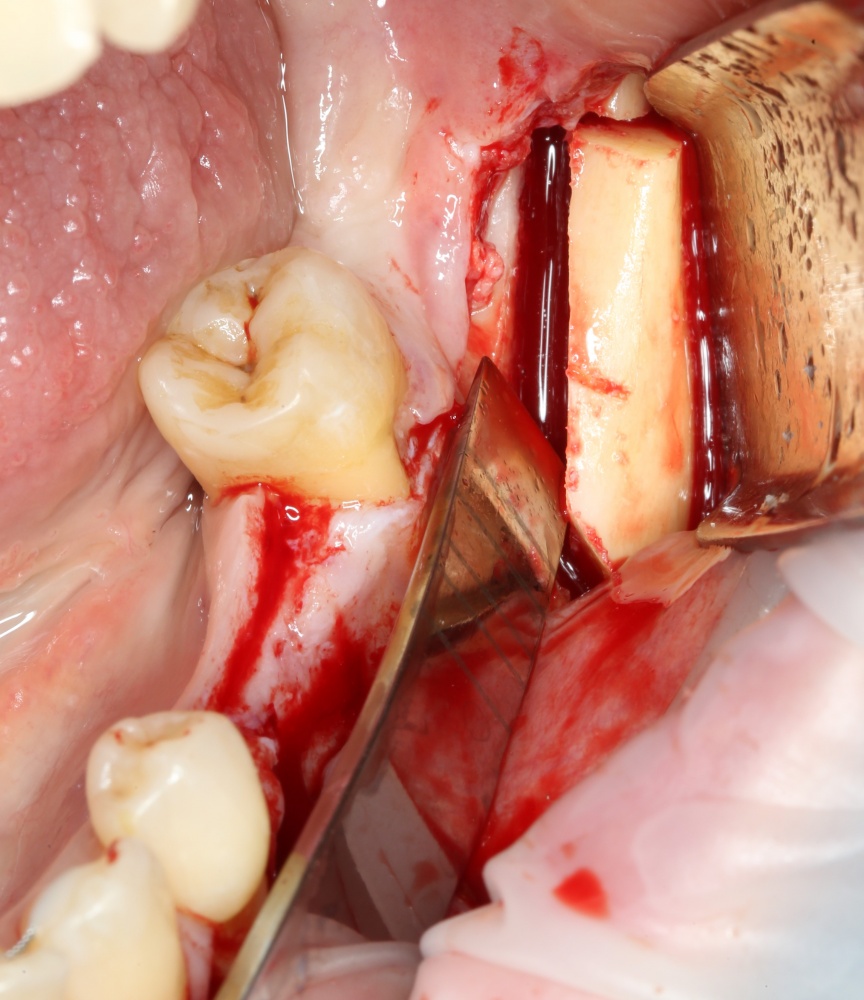

Следующим этапом происходит формирование и забор аутокостного фрагмента для пересадки:

A09A5447 (2) A09A5448 (2)

Правило простое: никаких физических усилий или молотков. Все делается исключительно нежно и аккуратно, легким движением руки. Вообще, если во время ЛЮБОЙ хирургической операции вам приходится прикладывать много физической силы — значит, вы что-то делаете не так. Имеет смысл проанализировать свои хирургические навыки)))

Далее, примеряем и адаптируем костный блок:

A09A5449 (2) A09A5450 (2)

Готовим его к фиксации:

A09A5451 (2)

Многие ошибочно предполагают, что большое количество дырок в блоке нужно для того, чтобы «всё лучше срослось». На деле, большое количество отверстий в аутокостном фрагменте даст нам возможность переставлять вины и адаптировать его «на месте». А это особенно важно для одномоментной установки имплантов, потому что винты не должны попасть в проекцию будущей лунки.

Фиксация костного блока:

A09A5452 (2) A09A5453 (2)

Для этого стоит использовать длинные винты. В противном случае, при подготовке лунки под имплантат костный блок может отлететь.